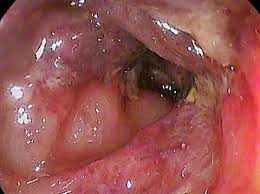

Pictured here is the appearance the colon can take in a patient with Crohn's disease

Cobblestoning